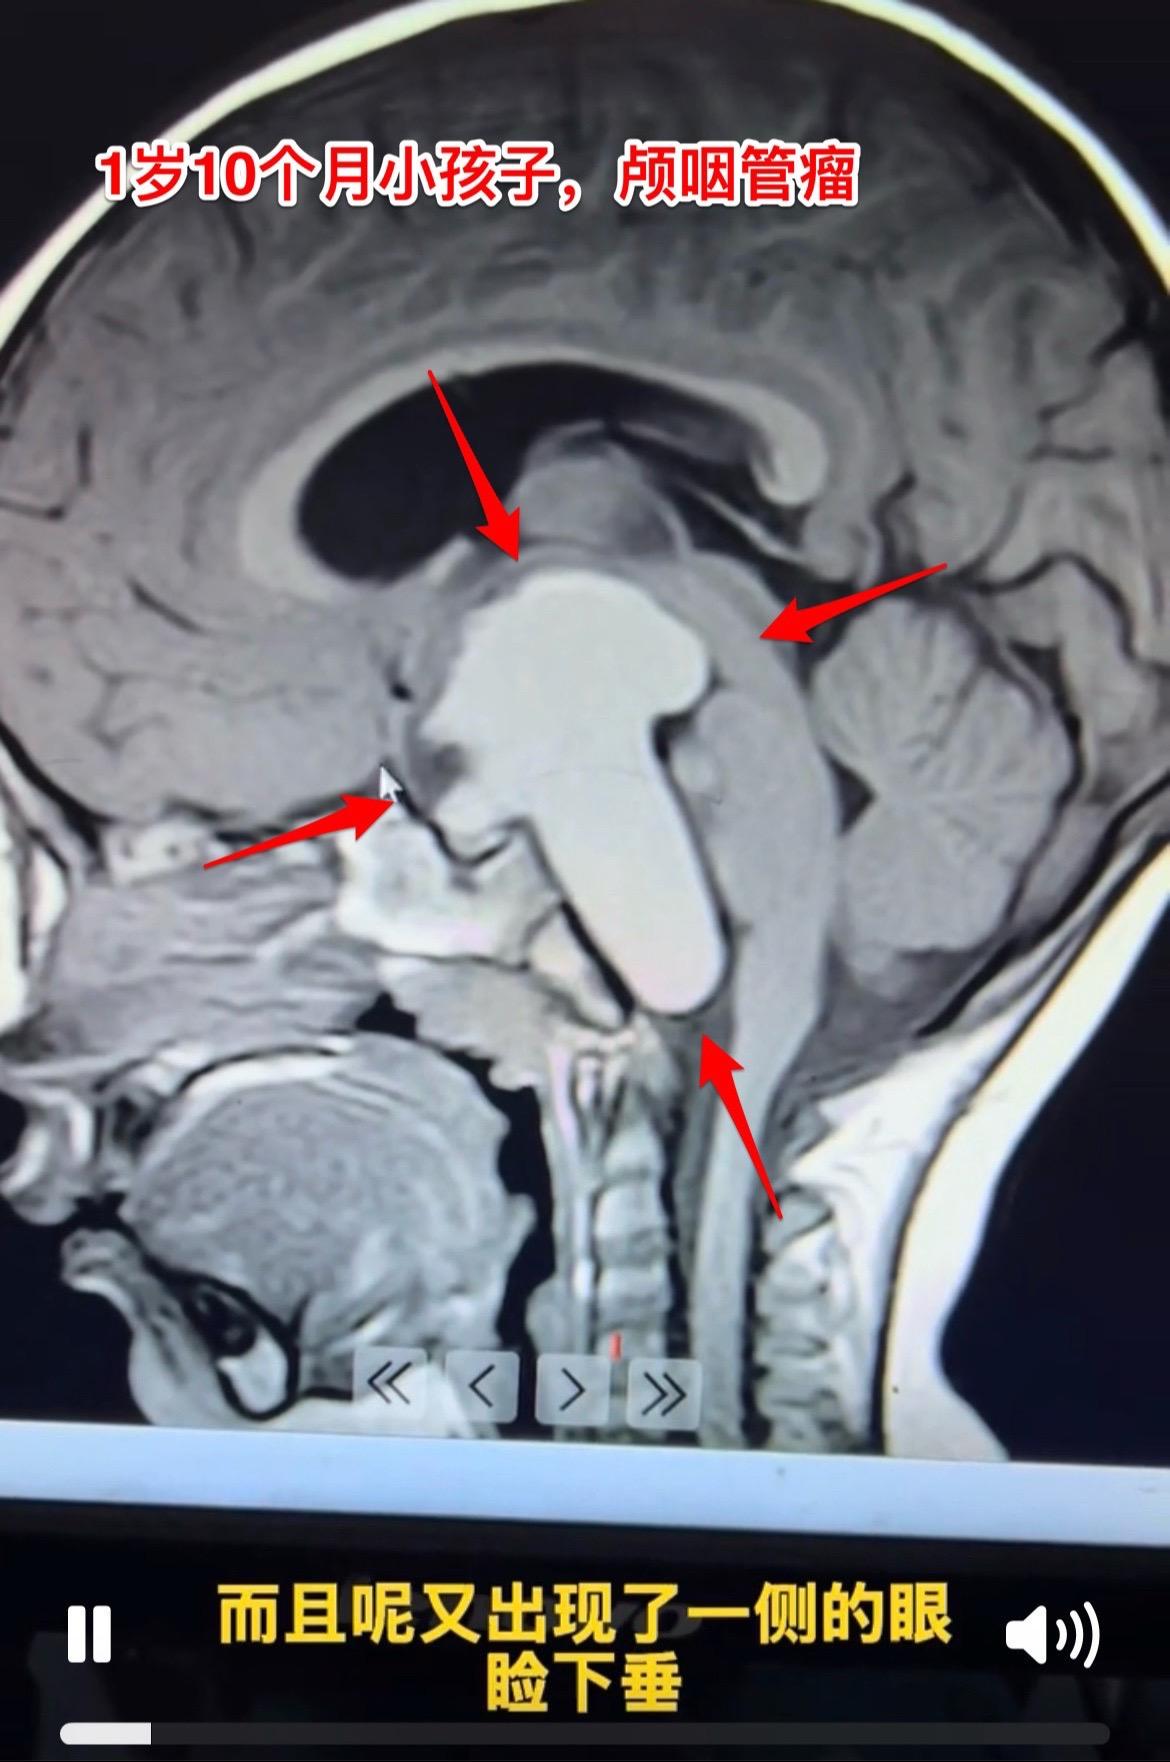

1岁10个月小孩子明天要作手术了。因为视力下降、眼睑下垂发现颅咽管瘤。 肿瘤的大小有多大?观众自己估量一下。 明天要给她作手术了,为她加油!预祝手术成功!